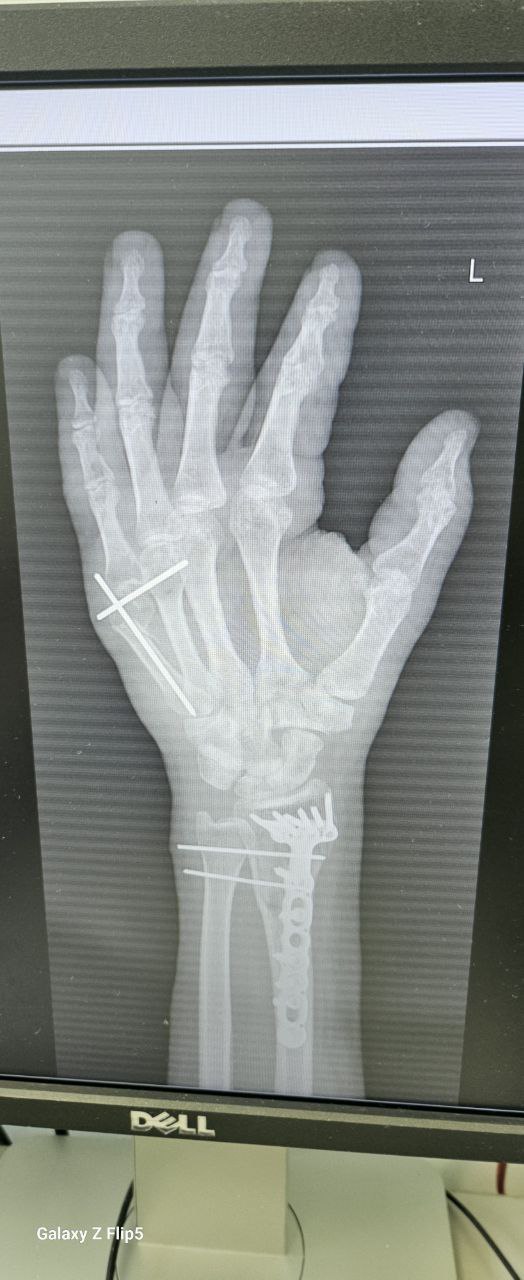

Полный экип хорошо отработал, но перчатки были дешёвые и без защиты запястья.

Восстановление заняло 5 месяцев. С ногой всё хорошо, рука работает, но последствия чувствуются.